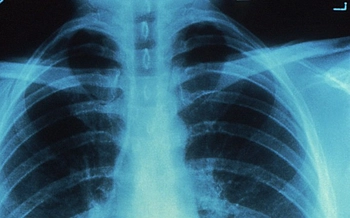

• Scientists discover how vitamin A drives the lung immune system to control TB

Scientists at Trinity College Dublin and St James’s Hospital, Dublin, have discovered how vitamin A drives the lung immune system to deal with tuberculosis (TB). The findings have just been published in a top respiratory journal, the American Journal of Respiratory Cell and Molecular Biology.